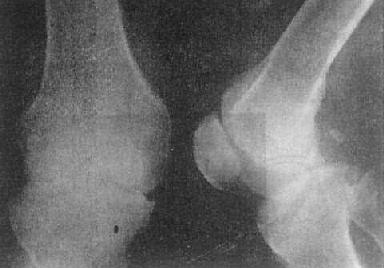

关节退行性变-膝关节退行性骨关节病

图2-1-16 关节退行性变-膝关节退行性骨关节病

膝关节的关节间隙变窄,边角锐利,有骨赘形成,关节面平而致密